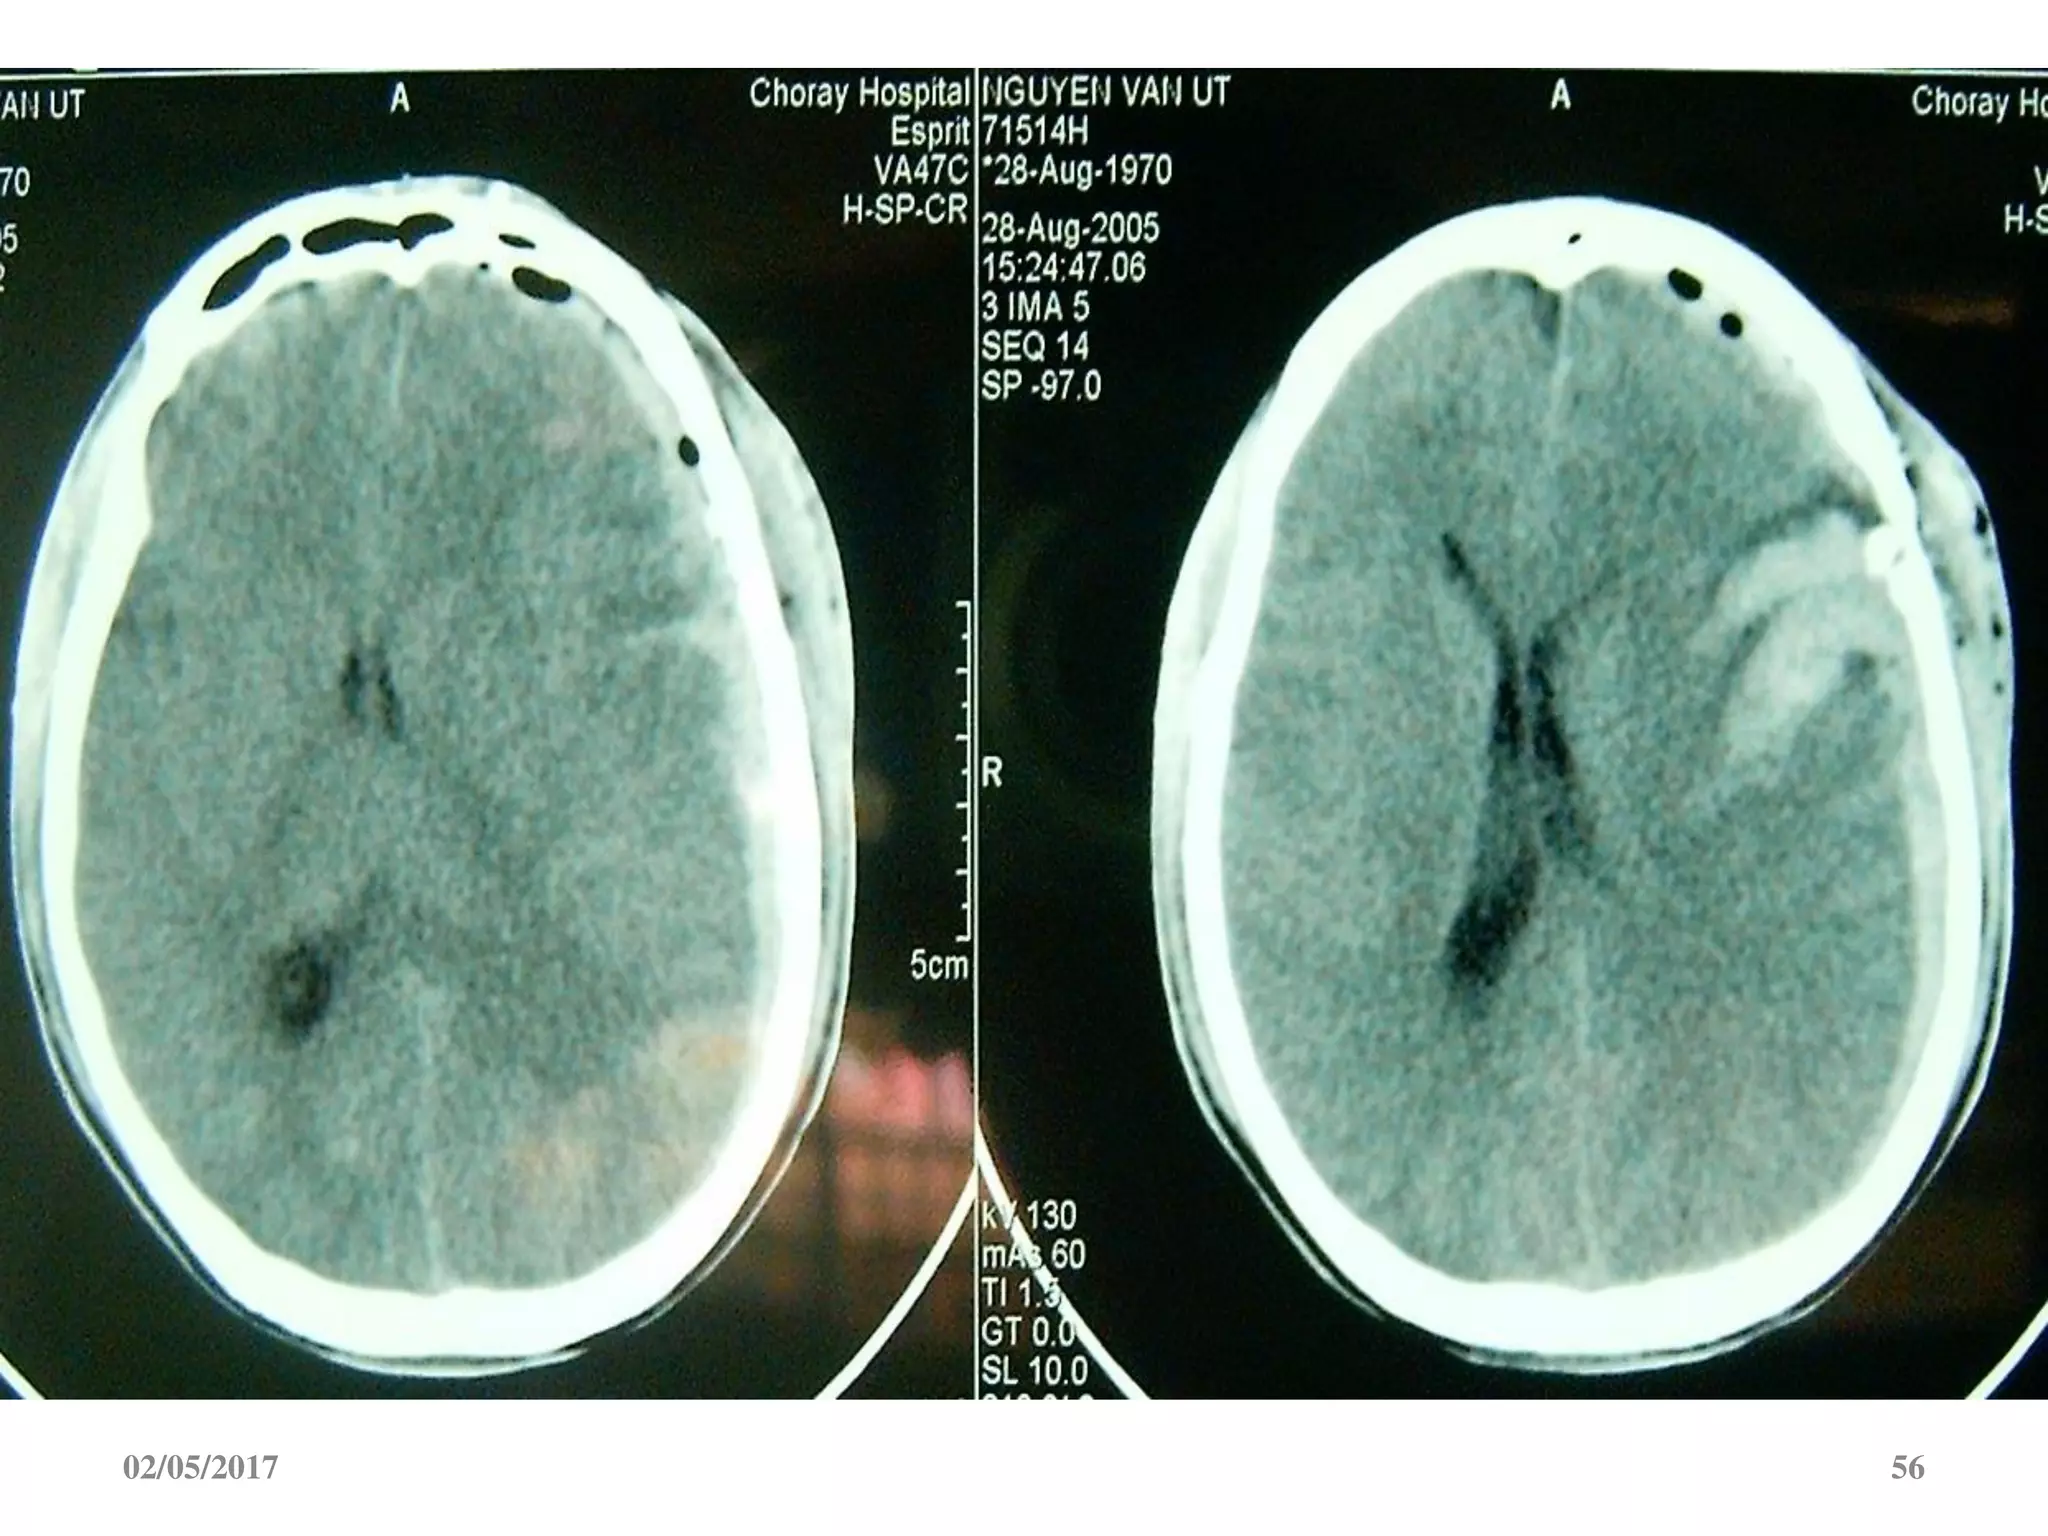

Máu tụ dưới màng cứng cấp

 Ngoài trục, hình liềm,

tăng đậm độ

 Vượt qua được các

khớp sọ

 Thường kèm dập não

02/05/2017 54

02/05/2017 56